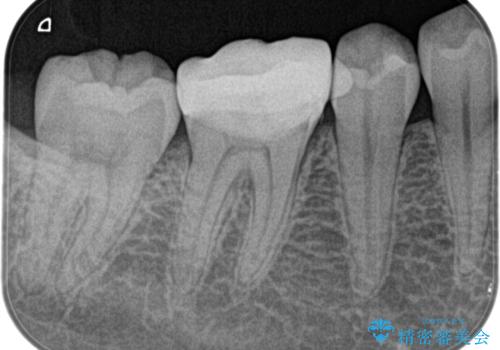

奥歯が痛い。精密根管治療〜オールセラミッククラウン